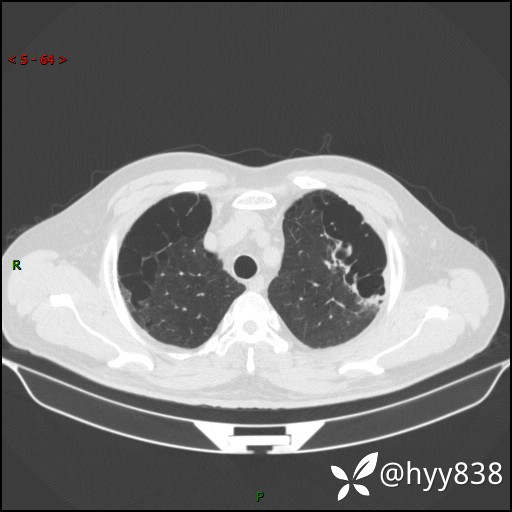

一周前胸部CT